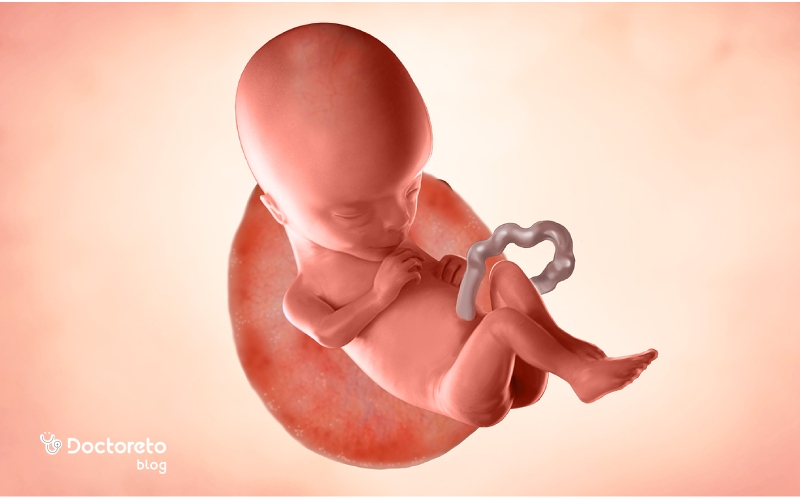

در هفته پانزدهم بارداری، جنین حدود ۹ تا ۱۰ سانتیمتر طول و نزدیک به ۷۰ گرم وزن دارد و بدن او بهتدریج متناسبتر میشود. سر هنوز نسبت به بدن کمی بزرگتر است، اما گردن مشخصتر شده و حرکات سر و بدن هماهنگتر میشوند. استخوانها در حال سفت شدن، عضلات قویتر و مفاصل فعالتر هستند. پوست جنین هنوز نازک و نیمهشفاف است و رگهای خونی از زیر آن دیده میشوند. در این مرحله، ابروها و موهای نرم روی سر و بدن (لانگو) شروع به رشد میکنند و گوشها تقریباً در جای اصلی خود قرار گرفتهاند. سیستم عصبی در حال بلوغ است و جنین میتواند حرکات خود را تمرین کند، هرچند مادر معمولاً هنوز آن را احساس نمیکند.

وضعیت جنین در هفته پانزدهم بارداری

در هفته پانزدهم بارداری، جنین به مرحلهای از رشد رسیده که حرکاتش منظمتر و اندامهایش کاملتر شدهاند. در این زمان، جنین حدود ۹ تا ۱۰ سانتیمتر قد و ۶۰ تا ۷۰ گرم وزن دارد و بدن او کشیدهتر و متناسبتر میشود. استخوانها و عضلات در حال تقویتاند و جنین میتواند سرش را بچرخاند، دستها و پاها را حرکت دهد و حتی حرکات مکیدن را تمرین کند. گوشها و چشمانش در جای طبیعی خود قرار گرفتهاند و پوست هنوز نازک و شفاف است. همچنین موهای ظریف (لانگو) سطح بدن را پوشانده و اندامهای جنسی خارجی تا حد زیادی تشکیل شدهاند، بهطوریکه در بسیاری از سونوگرافیها جنسیت قابل تشخیص است.

در هفته پانزدهم بارداری، جنین بهطور فعال در رحم حرکت میکند، اما این حرکات هنوز بسیار ظریف و غیرقابلاحساس برای مادر هستند. در این مرحله، عضلات و مفاصل جنین قویتر شدهاند و او میتواند دستها و پاهای خود را خم و راست کند، سرش را بچرخاند و حرکات بلع یا مکیدن را تمرین کند. گاهی در سونوگرافی، حرکات شبیه کشوقوس یا چرخیدن دیده میشود. مادرانی که قبلاً باردار بودهاند ممکن است زودتر از دیگران این حرکات خفیف را احساس کنند، اما معمولاً در هفتههای ۱۸ تا ۲۰ حرکات جنین بهطور واضحتر قابلدرک میشوند.

در هفته پانزدهم بارداری، جنین حدود ۹ تا ۱۰ سانتیمتر طول (از سر تا نشیمنگاه) و حدود ۶۰ تا ۷۰ گرم وزن دارد. در این مرحله، رشد بدنی او سرعت گرفته و نسبت سر به بدن متعادلتر میشود. استخوانها در حال سفت شدناند، عضلات قویتر شدهاند و حرکات جنین بیشتر و هماهنگتر میشود. اگرچه هنوز کوچک است، اما اندامها، صورت و حتی انگشتان دست و پا تقریباً شکل نهایی خود را پیدا کردهاند.